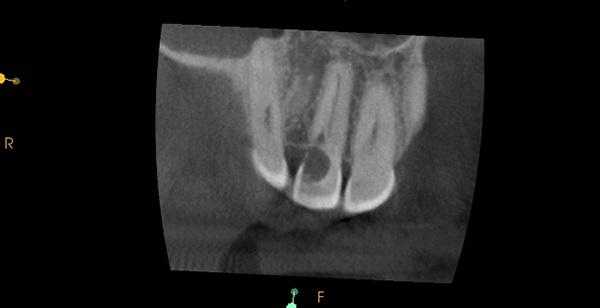

Фото 9. Подтверждение диагноза на КТ-срезе.

Фото 10. Распространение ИПКТ в парапульпарном апикальном направлении (срез КЛКТ).

По причине принципов получения рентгенологических изображений, двухмерной природы рентгенограмм и значительного перекрытия нескольких анатомических образований, периапикальные снимки, или снимки по типу bitewing, часто не являются достаточно чувствительными для диагностики ИПКР. Также информативность данных методов при ИПКР часто связана с объемом потери твердых тканей зуба. Конусно-лучевая компьютерная томография (CBCT) является особенно полезной на ранних этапах регистрации очага поражения, хотя учитывая, что данный метод редко используется с целью скрининга, ИПКР снова-таки часто диагностируется как дополнительная находка при диагностике каких-то других заболеваний или при планировании комплексных алгоритмов лечения. Пародонтальная потеря костной ткани крайне редко отмечается в области внешней пришеечной резорбции.

При рентгенологической идентификации ИПКР чаще всего напоминает кариозный дефект V класса. При локализации поражений со щечной или язычной сторон из-за графического наложения на область пульпы зуба они могут вызывать некую размытость ее контура. По мере развития патологии она прогрессируют к пульповой камере, не вызывая прямого воздействия на пульпу. В большинстве случаев, даже среди обширных поражений, твердые ткани, окружающие пульпу, часто выглядят почти неповрежденными, что на рентгенограмме проявляется в форме тонкой рентгеноконтрастной линии между дефектом ИПКР и пульпой зуба.

На КЛКТ внешняя резорбция проявляется как неравномерная рентгенопрозрачность и интактный канал зуба, внутренняя же резорбция выглядит как четкий очаг без прослеживания корневого канала.

КЛКТ с успехом применяется для определения внутренней резорбции и дифференциации ее от внешней. Обычная рентгенография часто не может выявить верный объем распространения, локализации и источник резорбтивного процесса. КЛКТ помогает в определении с тактикой лечения, а также предлагает составить верный прогноз на основе активности и распространенности поражения. И лечение, и результат лечения таким образом становятся более предсказуемыми.